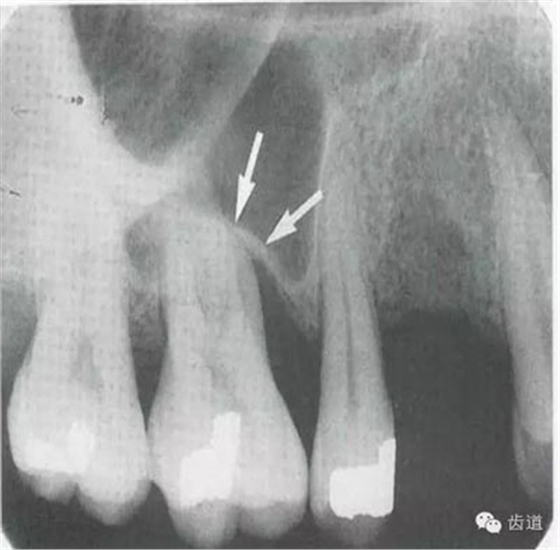

位于前磨牙根尖區(qū)域,為一大致圓形密度低的影像。頦孔位置變異大,多位于第二前磨牙根尖稍下,注意與根尖周病變區(qū)別,其要點(diǎn)是牙周膜及其骨硬板是否連續(xù)不斷。